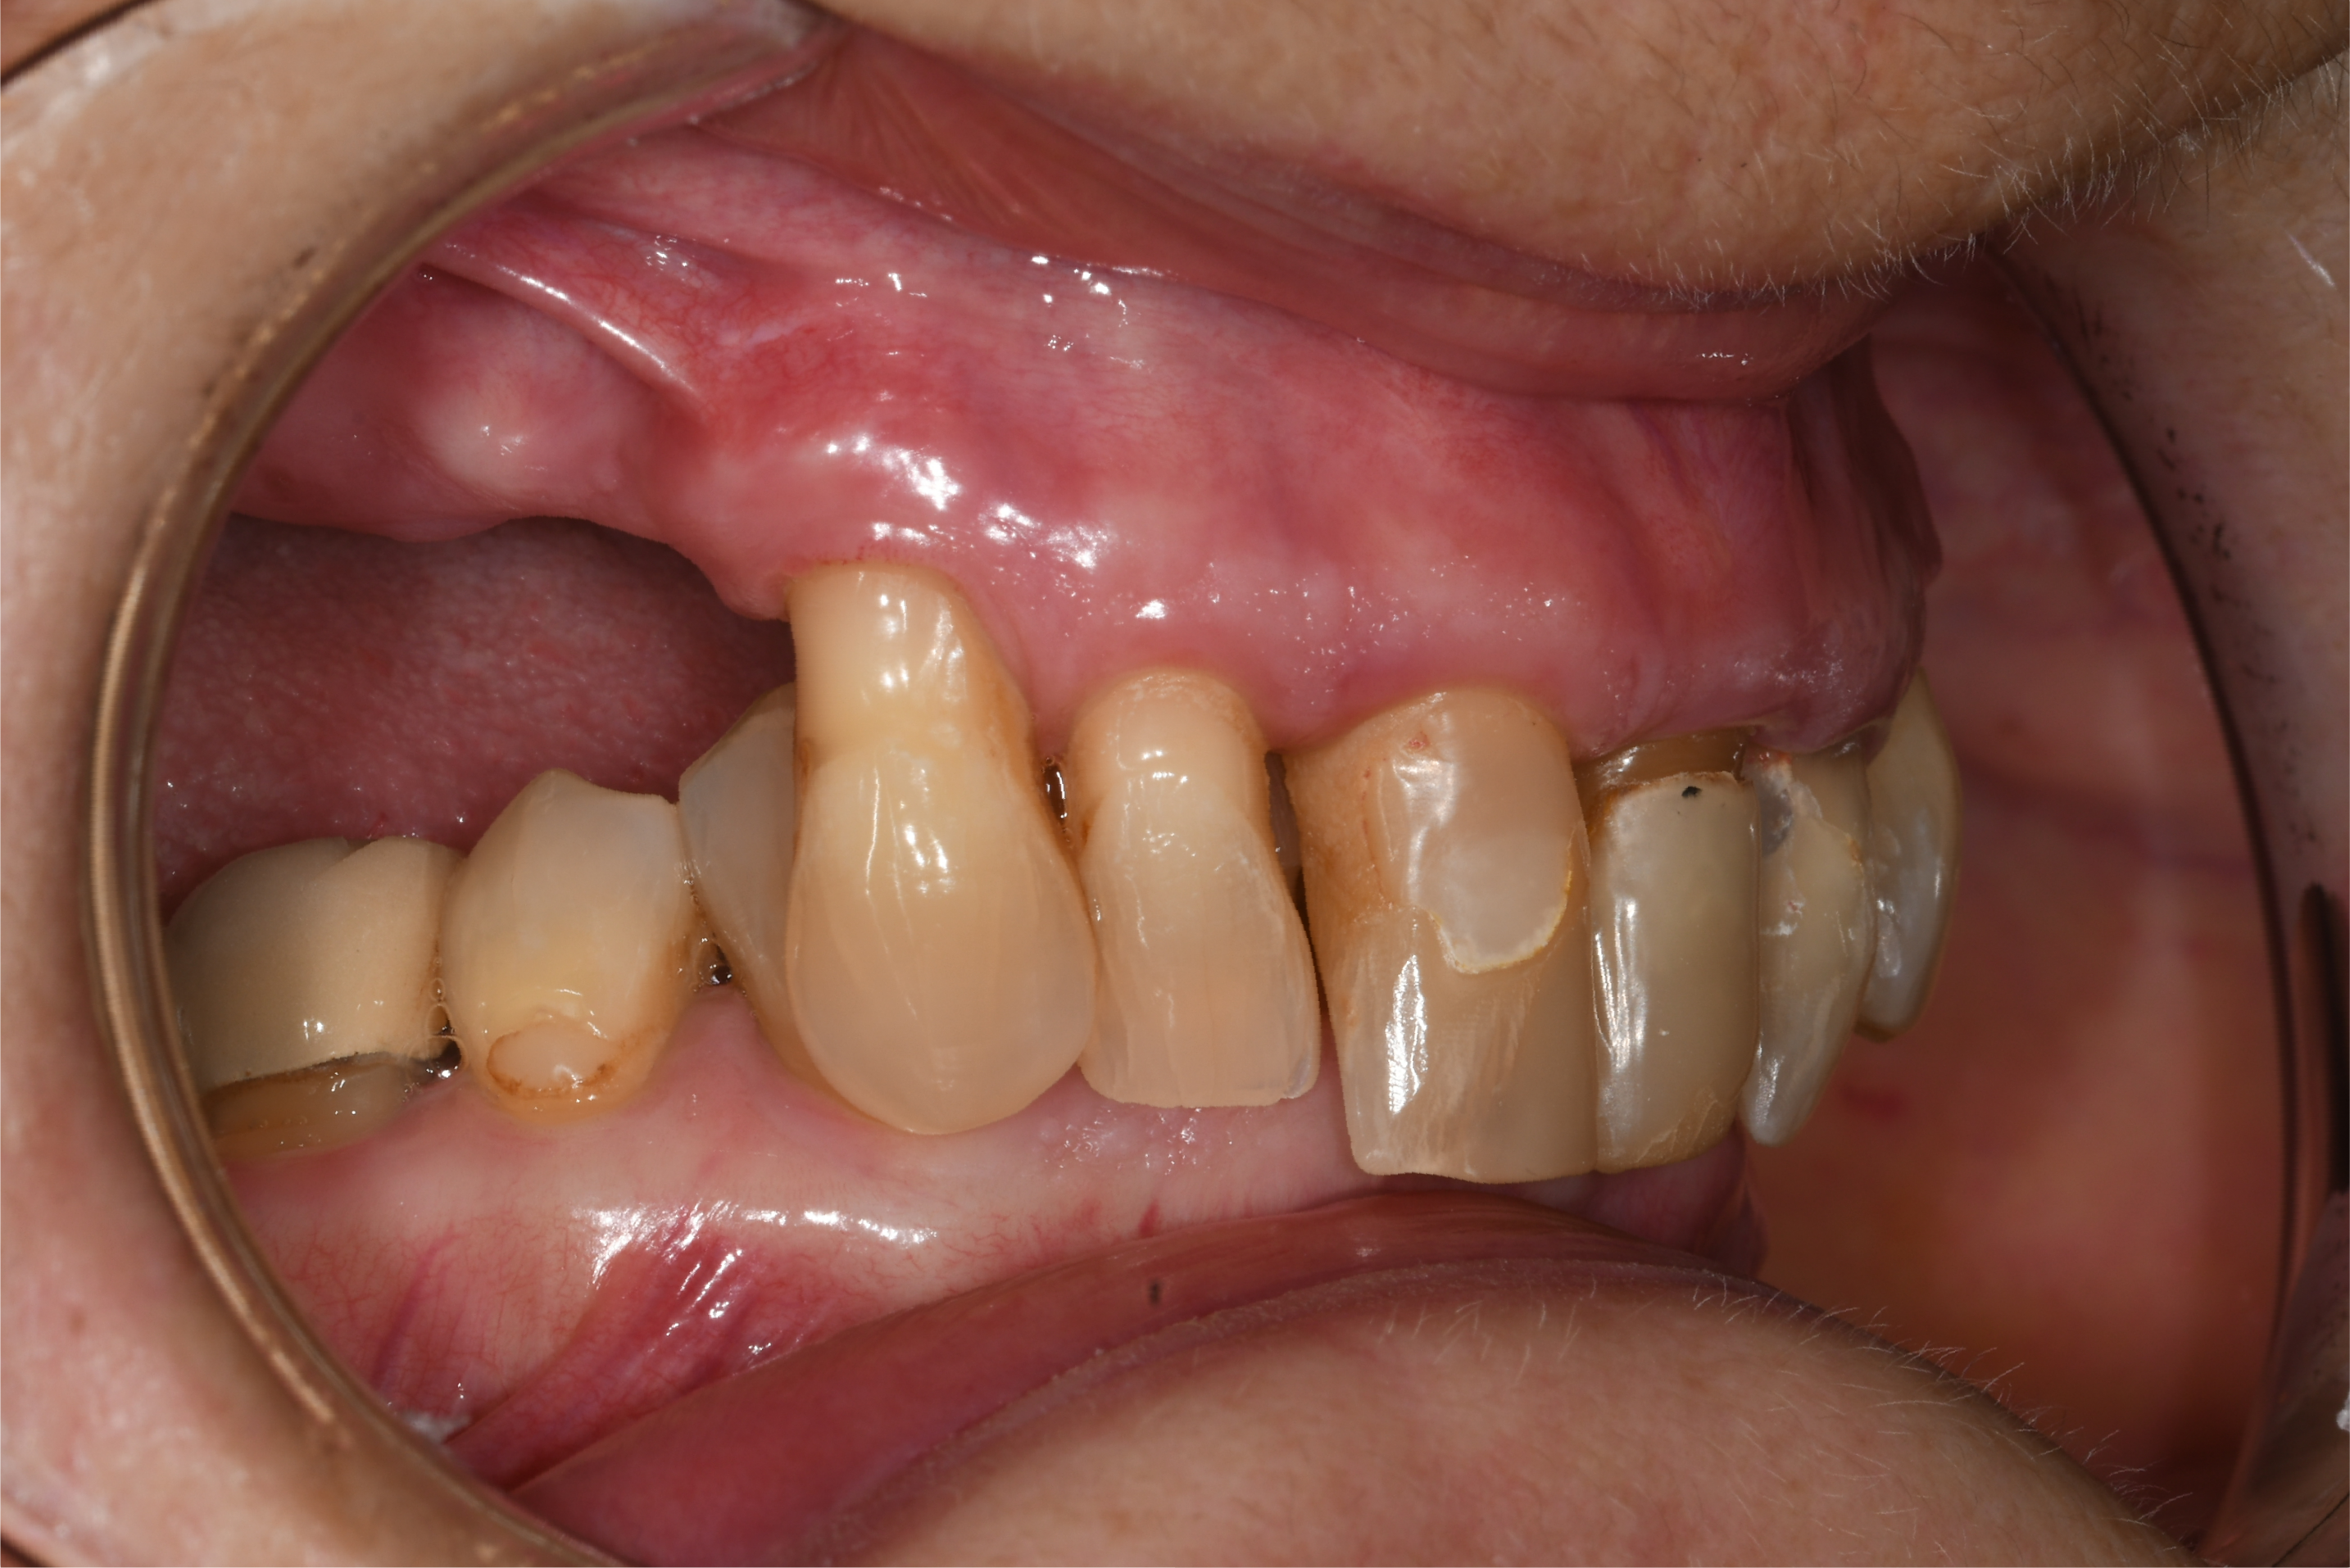

A 67-year-old female patient presented with a severely compromised anterior maxilla. Remaining teeth 13–23 showed advanced bone loss, periodontal breakdown, and a deep bite. The teeth were deemed non-restorable. The patient experienced functional limitations and significant aesthetic concern. Medical history was unremarkable.

Surgical Procedure

Following the extraction of teeth 13–23, the tooth-supported guide was positioned and stabilized, allowing precise, fully guided implant surgery. Multi-Unit Abutments were inserted according to the digital plan. Immediately post-surgery, intraoral photogrammetry was performed to record the implant positions with high accuracy, eliminating the need for conventional impressions or splinting.